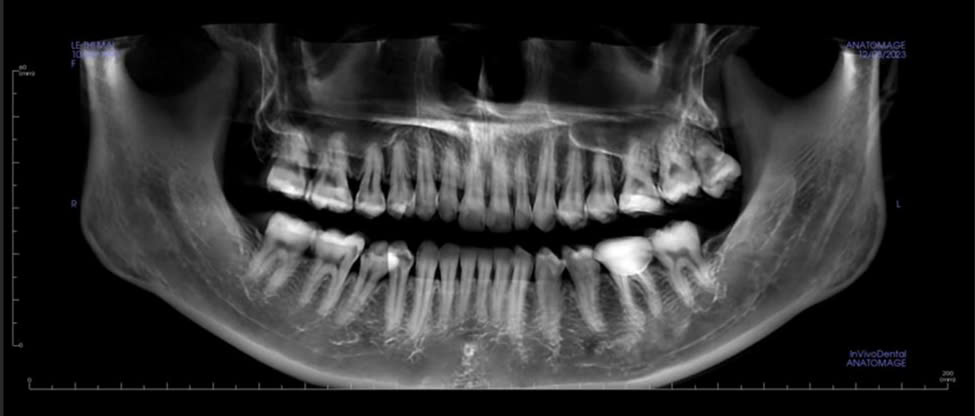

ĐIỀU TRỊ NỘI NHA KHÔNG PHẪU THUẬT ĐỐI VỚI CÁC RĂNG CÓ TỔN THƯƠNG QUANH CHÓP LỚN

Viêm quanh chóp là tổn thương viêm của các thành phần mô học vùng quanh chóp răng. Đây là kết quả của phản ứng viêm với sự xâm nhập của vi sinh vật và độc tố của chúng trong hệ...